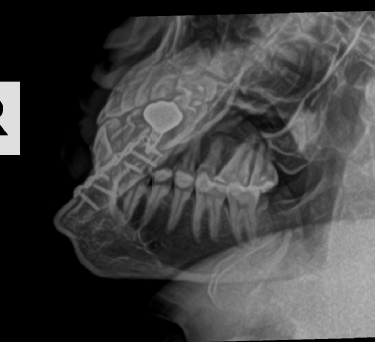

The story of how I got the x-ray or at least the whole scenario was kind of funny. I broke my pinky somehow at my friend's house in Oklahoma in the fall of 2023. When I went to the doctor they did an x-ray of my hand. I have a few metal parts in my head and then told them I got into a fight and thought I may have hurt some implants in my head. Not really but I just wanted these X-rays.